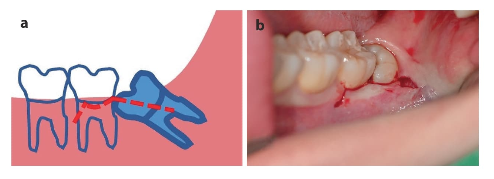

En muchos casos, no logran erupcionar completamente o lo hacen en posiciones inadecuadas, lo que se conoce como impactación. Esta condición puede desencadenar infecciones, dolor, inflamación e incluso afectar a los dientes vecinos. Además, su difícil acceso complica la higiene, favoreciendo la acumulación de bacterias.

No todas las extracciones son iguales. Cuando el diente está completamente visible en la boca, el procedimiento suele ser más sencillo. Pero cuando está parcial o totalmente cubierto por encía o hueso, se requiere una exodoncia quirúrgica.

- Impactaciones profundas o en posiciones anguladas